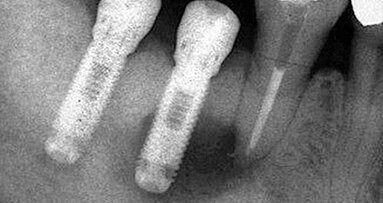

Cílem retrospektivní kohortové studie bylo zhodnotit střednědobou úspěšnost (3–5 let) a úbytek marginální kosti tissue level (TL) implantátů Oktagon® (DRS International GmbH, Langenfeld, Germany). Jedná se o titanové screw type implantáty s hrubým povrchem (sand blasted and acid etched) a s leštěným 1,8 mm vysokým krčkem. Spojení mezi fixturou a abutmentem je realizováno vnitřním konusem s protirotačním osmihranem.

Mezi 1. 6. 2011 a 31. 10. 2012 bylo zavedeno jedním implantologem 390 TL implantátů Oktagon® u 155 pacientů. Chirurgický postup byl dvoudobý s uzavřeným hojením a druhou chirurgickou fází za 6–8 týdnů od implantace. Implantáty byly zatěžovány definitivní protetickou prací 8–12 týdnů po zavedení. Implantáty byly zavedeny s rozhraním leštěného a hrubého povrchu mírně subkrestálně. Do studie byly zařazeny pouze fixtury o průměru 4,1 mm a délky 10 mm (4,1/10). Vylučovacími kritérii byla anamnéza radioterapie v oblasti hlavy a krku, užívání bisfosfonátů, dekompenzované celkové onemocnění (ASA skóre > III)3, implantace do augmentovaného místa, imediátní implantace a doba sledování kratší než 3 roky. Důvodem k vyloučení ze studie nebylo: pohlaví a věk pacientů, léčené komorbidity, kouření ani historie periodontitidy. V uvedeném období bylo zavedeno 192 TL implantátů rozměru 4,1/10 u 86 pacientů. Do studie bylo zařazeno 151 implantátů u 72 pacientů (do studie nebylo zařazeno 32 implantátů zavedených do augmentovaného místa a 9 imediátně zavedených fixtur). Během pravidelných kontrol bylo zhotoveno kontrolní OPG 3–5 let od zavedení implantátů. Na kontrolním RTG byl změřen úbytek marginální kosti (MBL) u každé fixtury meziálně a distálně, do hodnocení byla vždy zahrnuta vyšší hodnota. Při měření byl jako referenční bod použit přechod mezi krčkem implantátu a abutmentem, protože je dobře identifikovatelný. MBL byl určen odečtením známé výšky krčku implantátu (1,8 mm) od vzdálenosti referenčního bodu a místa prvního kontaktu implantátu s kostí4, 5, 6, 7. RTG bylo kalibrováno změřením každé fixtury8. Klinickým vyšetřením byla zhodnocena subjektivní spokojenost pacienta s rekonstrukcí, pevnost protetických prací a stav měkkých tkání v okolí krčku implantátů. Opakovatelnost měření MBL byla ověřena zaslepeným kontrolním měřením třiceti náhodně vybraných RTG s odstupem 12 měsíců. Bylo dosaženo dobré shody obou měření (Pearson R = 0,98, p < 1 × 10-6). Měření MBL bylo prováděno s rozlišením 0,1 mm i když použitý software (Planmeca Dimaxis Pro) umožňuje měření s rozlišením 0,01 mm, není tato přesnost v reálných podmínkách dosažitelná9. Hodnoty uváděné se dvěma desetinnými místy vznikly při výpočtech. Studie byla provedena v souladu s požadavky Helsinské deklarace10. Všechna data byla pro statistické zpracování anonymizována.